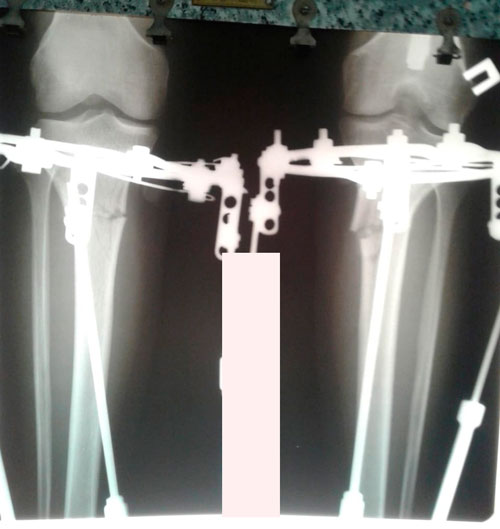

5 - ый день круток

Вложения

IMG_1002-10-02-19-11-25.JPG

IMG_1001-10-02-19-11-25.JPG